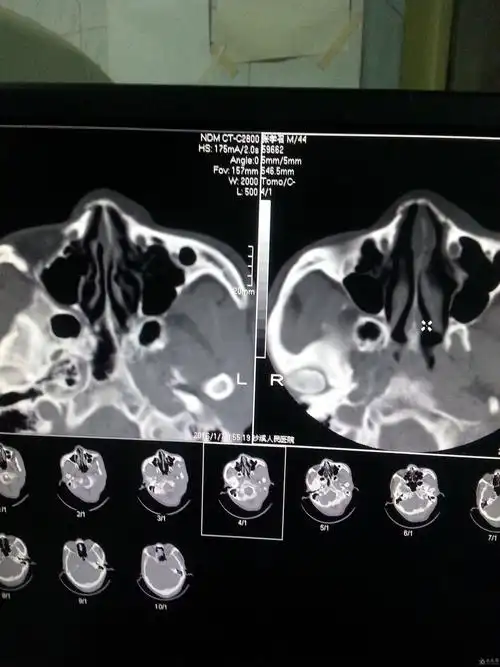

鼻骨骨折影像学诊断

鼻骨骨折了吗

本人学生有个鼻骨骨折帮忙老师们看下伤到什么程度